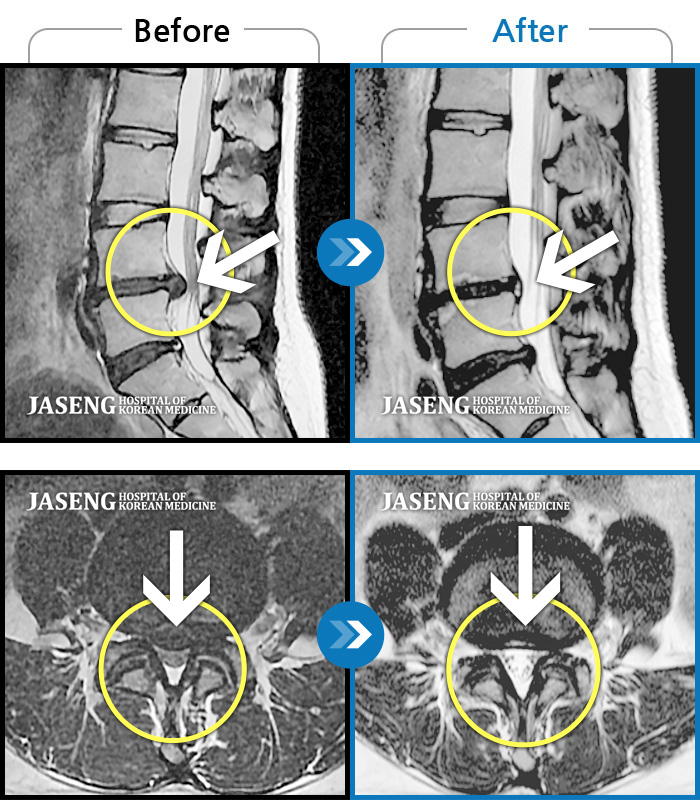

Before

After

환자에게 사전 동의를 받아 동일 조건에서 촬영되었습니다.

개인에 따라 치료 후 부작용이 발생할 수 있으니 의료진과 상담 후 치료를 진행하시기 바랍니다.

허리 골반 통증, 앉을 때 우측 다리 당김 및 저린 증상

서 있거나 보행시 엉덩이 통증